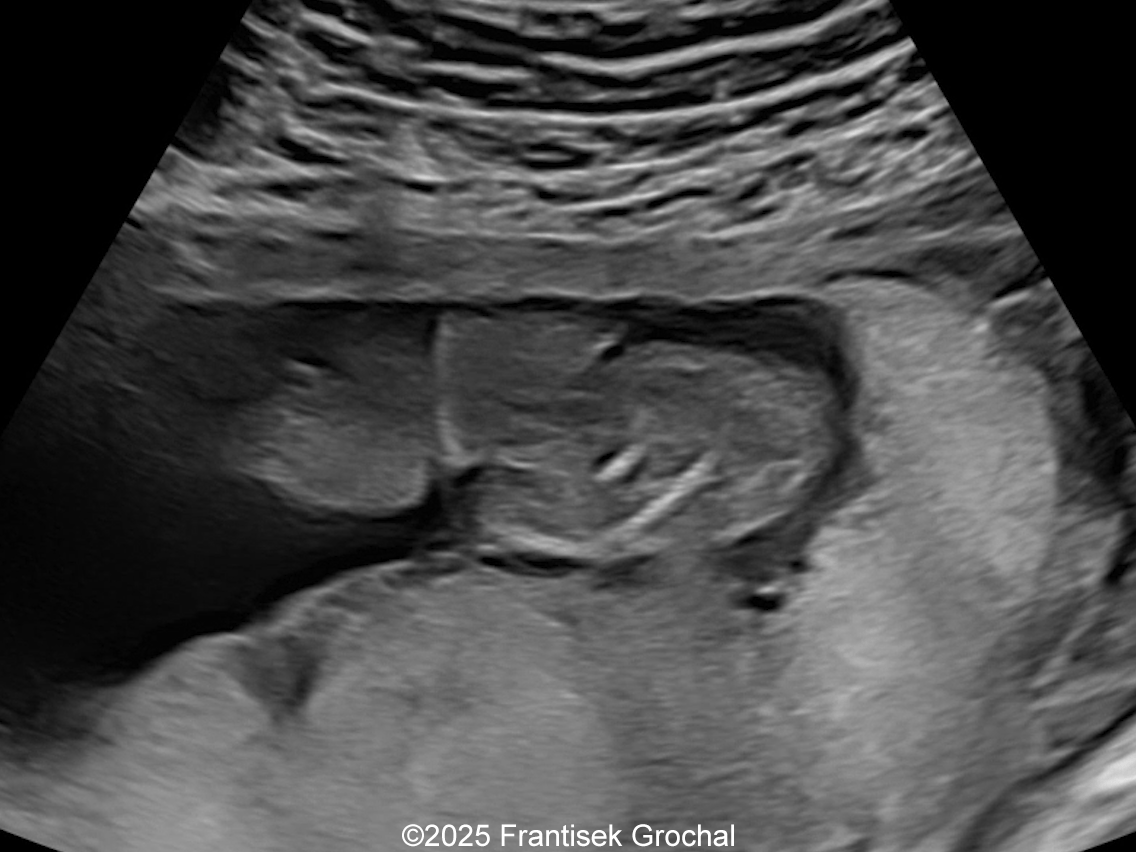

Image 2

We present a case of Amniotic Band Sequence seen in 21st week of pregnancy. The fetus showed the following findings:

• Constriction of the right thigh by the amniotic band

Constriction of the right thigh by the amniotic band

Image 2 Constriction of the right thigh by the amniotic band